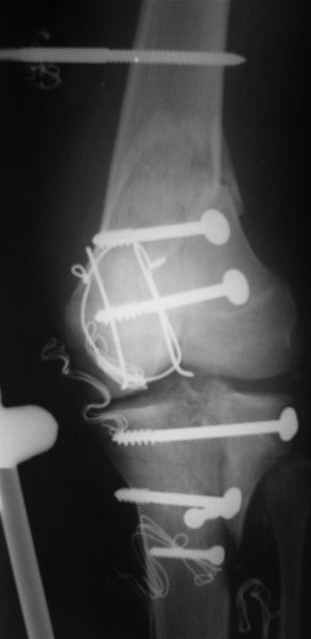

На снимке № 1 вид раны,

№2 покрытие губкой,

№3 финальное закрытие пленкой и после включения вакуума,

№4 снимок через два дня после операции, супракондилярный перелом, при поступлении конечность была холодная и без пульса, подозрение на повреждение сосудов, сделана ABI (ankle-brachial index) в приемном отделении, индекс меньше 1 к 0.9 в норме 1 к 1.1, срочная ангиография в операционной после Ex-Fix, по два стержня в сегменте наложен в течение 20 мин, повреждение подколенной артерии, ушивание сосудистым хирургом через медиальный доступ в дистальном отделе бедра и двухразрезная профилактическая фацсиотомия, перкутанная фиксация каннюлированными шурупами несмещенного перелома шейки бедра и дополнительные стержни в фиксаторе для жесткости.